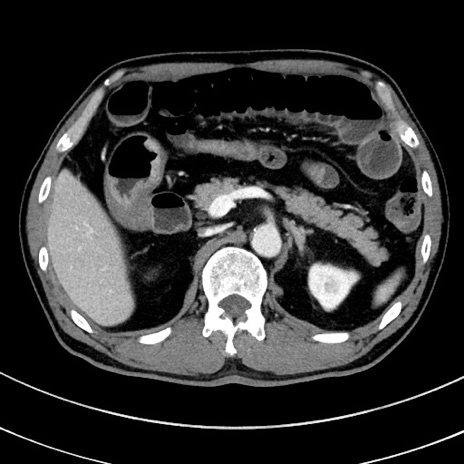

冠状断像

【症例】 60歳代男性

【主訴】 黒色吐物

【現病歴】 4日前から嘔気自覚、2日前の朝食後にも嘔気あり、自分で手で嘔吐反射起こし嘔吐したところ血が混ざっていたため受診。

【既往歴】 5年前汎発性腹膜炎を伴う急性虫垂炎で手術、高血圧、前立腺肥大症、高脂血症

【身体所見】 腹部正中に手術癩痕あり 腹部平坦・軟圧痛なし膨満感あり

【データ】WBC 8400、CRP 4.54